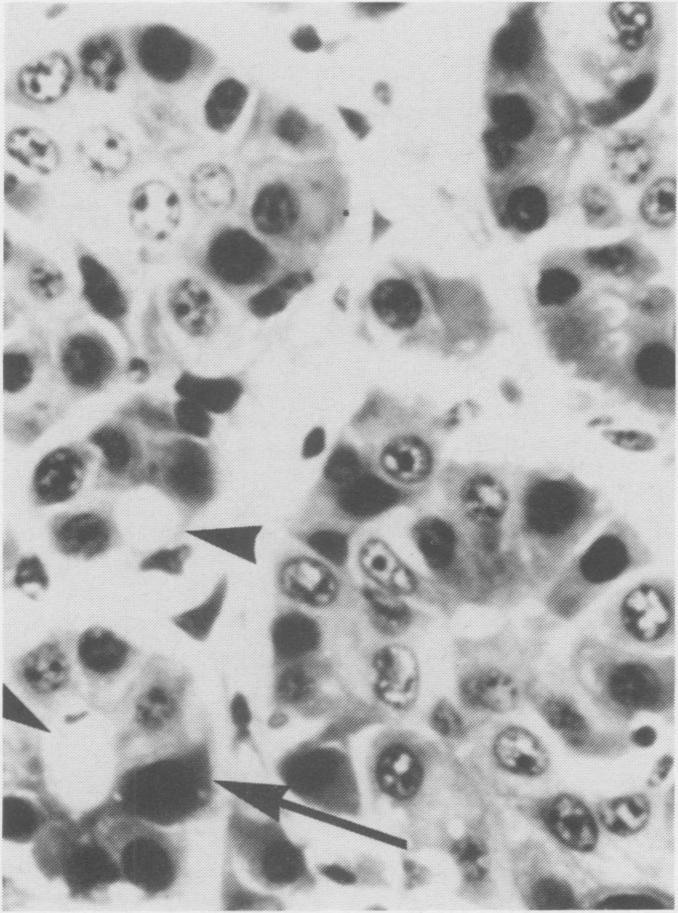

Eight bovine, two ovine and one porcine primary hepatocellular neoplasms were found during a five year survey of tumors from meat packing plants. The tumors varied in size and usually were yellow-grey. Some were encapsulated and divided into lobules by fibrous septa. The tumor cells closely resembled normal hepatocytes and were arranged in a trabecular pattern or in sheets with caverns or were a mixture of the two. Eosinophilic intranuclear inclusions were present in one bovine and one ovine case.